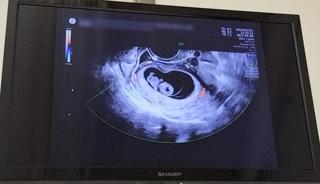

写真:9w3d:とまるみさん

頭殿長22.4ミリ。

妊娠5週〜8週はずっと茶色の出血があり自宅安静の日々を過ごしていたため、ものすごく心配していましたが、順調とのことでホッとしました(*^^*)

小さいけど頭、胴体、手足がはっきり分かりました。

胴体の真ん中の心臓がピコピコ光っているのを見ていると、愛おしさが込み上げました。

1年の不妊治療を経てやっとやっと授かった子なので、本当に嬉しい気持ちでいっぱいになりました。